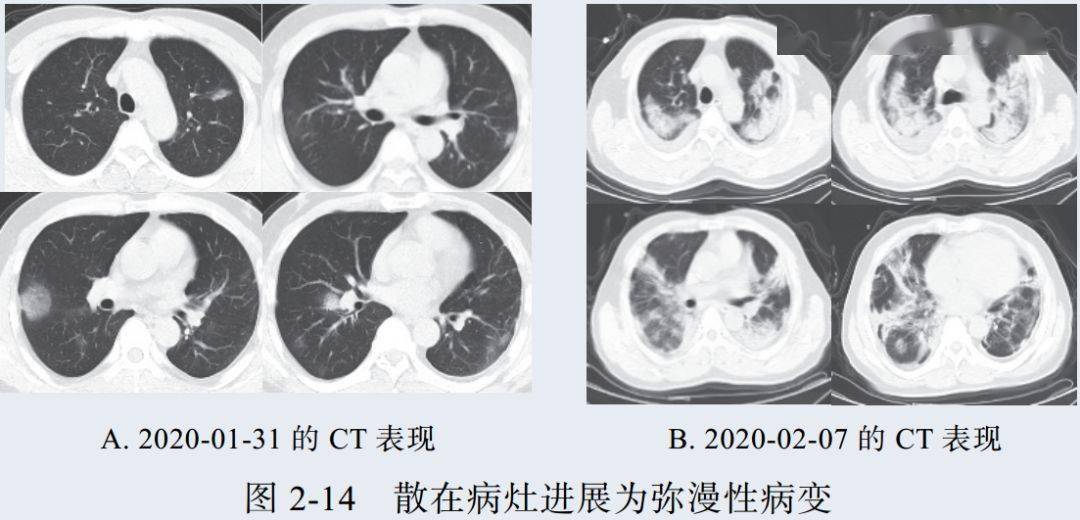

二、进展期征象

新冠肺炎大多数病例进展迅速,复查 CT 影像发生明显变化

表现为病灶数目明显增多,范围明显扩大,密度增高,病灶分布由外周向中央推进

根据既往 SARS 病理学机制,提示为肺泡腔内聚集大量细胞渗出液、间质内血管扩张渗出;肺泡连通起来形成融合态势(图 2-11)

图 2-11 病灶数目增多、范围扩大 (A-D)